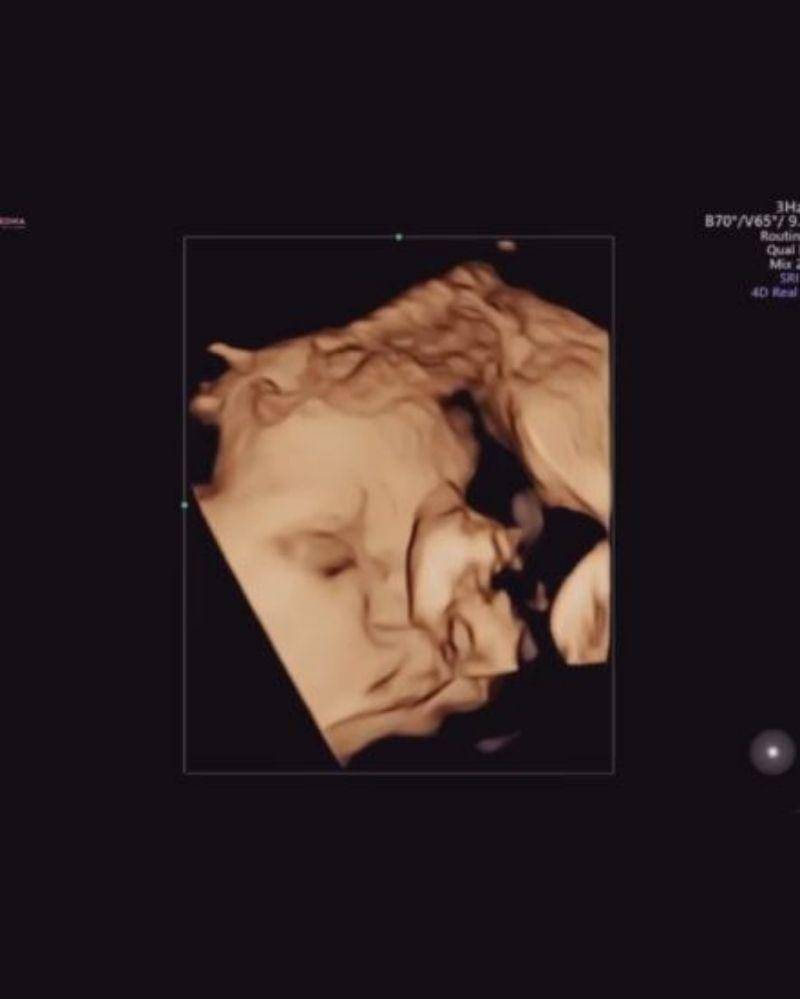

31. Nadi Djiwa Anggara, anak Nadine Chandrawinata dan Dimas Anggara

Nah, kalau ini potret USG Nadi Djiwa Anggara, putri pasangan Nadine Chandrawinata dan Dimas Anggara. Sama dengan Baby Ameena, Baby Djiwa juga lahir di tanggal cantik, yakni 22-2-2022.

Banyak warganet yang bilang Baby Djiwa sudah mirip sang Mama sejak masih di dalam kandungan. Mama setuju nggak nih?